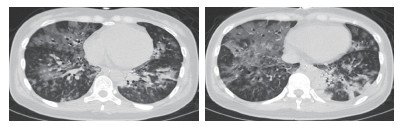

患者女性,29岁,以“恶心、呕吐1个月余,进食困难伴饮水呛咳半月,呼吸困难5 d,发热1 d”主诉收入北京世纪坛医院。患者病史长且复杂,笔者根据其先后就诊医院对其病史进行总结(表 1)。2018年5月10日患者在北京西客站候车过程中出现呼吸困难加重,随后出现呼之不应,立即送至本院急诊。至本院急诊抢救室时,患者生命体征心律166次/min,呼吸32次/min,血压80/47 mmHg(1 mmHg=0.133 kPa),氧饱和度80%,体温39.5℃,查体:浅昏迷,双瞳孔等大正圆,直径约2 mm,对光反射存在,无颈项强直,口周及口腔内可见较多清亮唾液,双肺呼吸音粗,双肺可闻及少量湿性啰音,左下肺为著,心律齐,各瓣膜听诊区未及杂音。腹部查体未见异常。双侧腱反射存在,双侧病理征阴性。血气:pH 6.95, PCO2 88 mmHg, PO2 48 mmHg, Lac 8.0 mmol/L, 故立即予气管插管、呼吸机辅助通气, 建立静脉通路补液及去甲肾上腺素泵入升压治疗,并立即收入本院急诊ICU。患者入院后主要血化验结果见表 2。心脏彩超提示弥漫性室壁运动异常,EF为45%,考虑感染相关心肌抑制。胸部CT提示双肺弥漫大小不等点片、斑片状高密度影,其内可见支气管走行,纵隔内可见多个大小不等淋巴结影,考虑双肺感染(图 1)。下肢血管超声、头颅CT、腹部CT均未见明显异常。患者入院后继续予气管插管接呼吸机辅助通气,呼吸机模式PC,起始参数:P 18 cmH2O(1 cmH2O=0.098 kPa),f 14次/min,PEEP 4 cmH2O,FiO2 40%;去甲肾上腺素静脉泵入及静脉补液升压治疗;肠内营养治疗;结合患者胸部CT及其他化验结果,诊断首先考虑重症肺炎,脓毒症,脓毒性休克,Ⅱ型呼吸衰竭,因此抗感染采用联合抗细菌、真菌及病毒全覆盖方案,同时予静脉输注人免疫球蛋白(IVIg)20 g/d ×5 d,静脉输注甲泼尼龙80 mg/12 h×4 d→40 mg/12 h×7 d→40 mg/d×3 d→甲泼尼龙片20 mg/d口服。经过上述治疗,患者体温逐渐下降至正常,神志逐渐转清,四肢肌力逐渐恢复至正常,呼吸机条件逐渐下调至模式PS,参数P 8 cmH2O,FiO2 40%,循环逐渐稳定并停用血管活性药物。复查主要血化验结果(表 3)均较前好转。抗感染治疗后前后2次复查胸部CT均提示肺炎较前吸收好转(图 2)。此时患者能脱机,但却不能拔管,且患者无咳嗽反射亦不能遵嘱吞咽。

图 1 患者入院后首次胸部CT检查结果(2018-05-11)